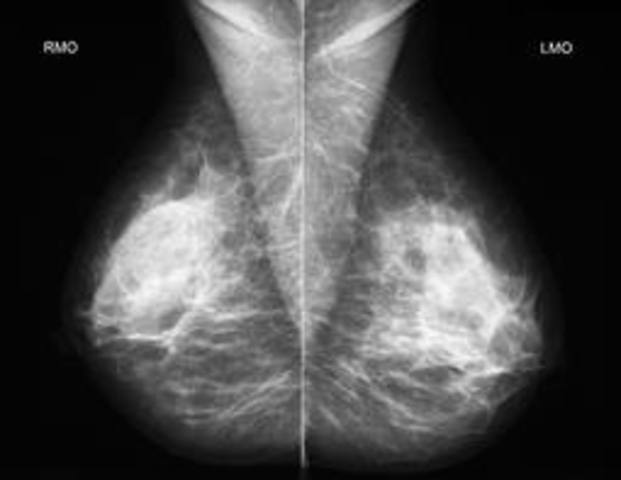

• yearly mammograms

yearly mammograms

Yearly mammograms are recommended starting at age 40 and continuing for as long as a woman is in good health,A mammogram is a picture of your breast taken with a safe, low-dose X-ray machine. It's the most effective exam for early detection of breast cancer.